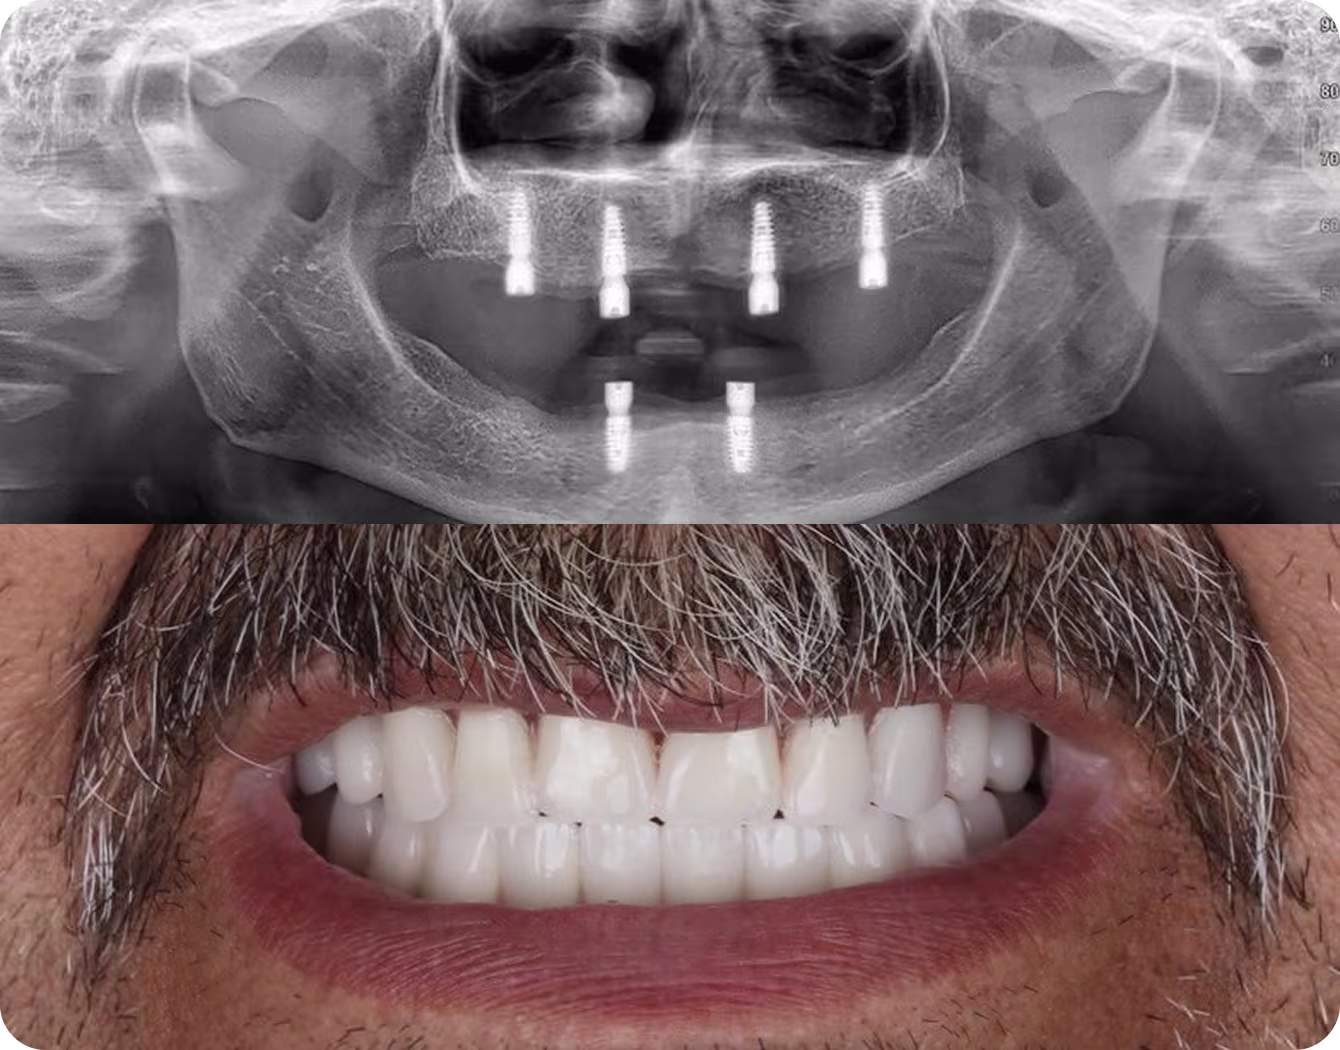

(Fixed, Non-Removable)

Permanent, beautiful, and built to last